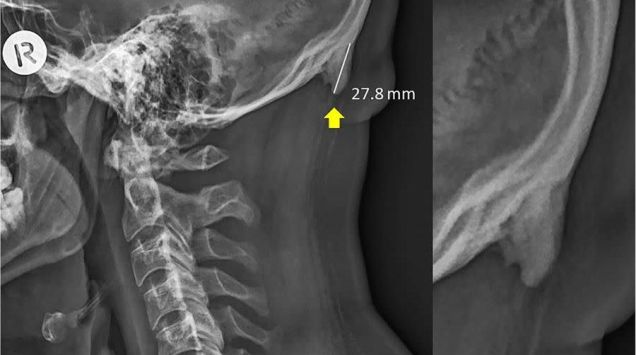

You might have heard recently, from publications like the Washington Post, NBC, and of course, Newsweek, that some people are growing a “horn” or a “spike” out of the back of their skull from using a smartphone too much.